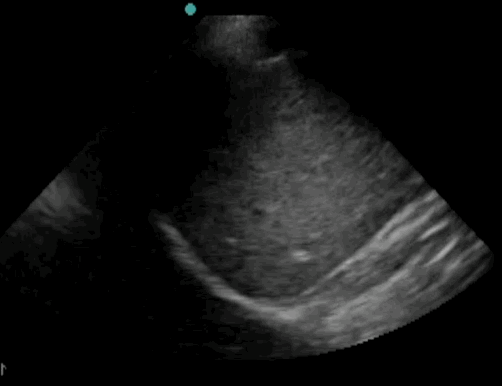

10_Heart_SC

Pericardiel effusion

10_Heart_SC – Pericardiel effusion